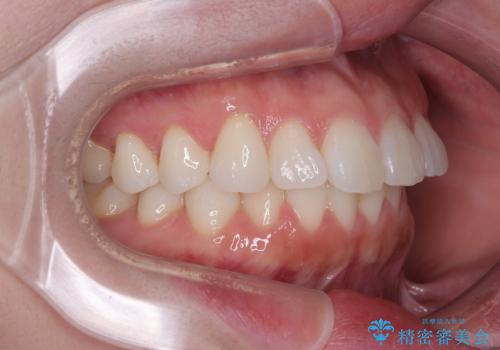

- 上下前歯の叢生を気にして来院された患者様です。

軽度な叢生であり、安価で短期間の治療を規模されていたため、インビザライン・モデレートを用いて矯正治療を行うこととしました。

インビザライン・モデレートは、製作できるアライナーの枚数に制限があるため、移動可能な量に限りがあるものの、インビザライン・ライトよりも枚数が多いため、幅広い症例に対応可能です。